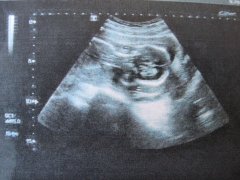

习惯性流产多是频繁人流造成的,也可能是子宫内膜壁较薄造成的,女性习惯性流产需要到医院做详细检查,了解具体原因对症治疗能有效改善,积极治疗原发性疾病,并且怀孕早期要做好相应的护理工作,那么,习惯性流产的诱因有哪些?